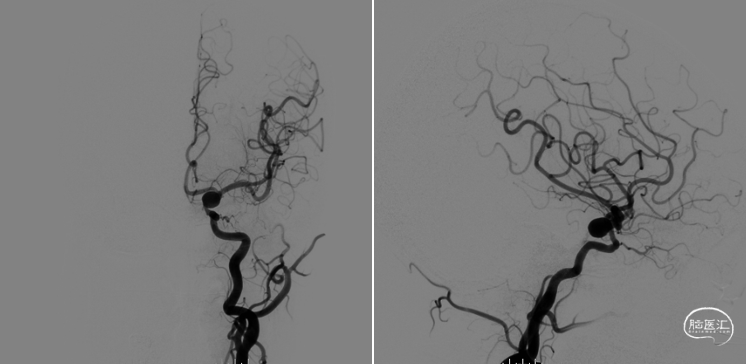

双侧椎动脉造影。

右侧颈总动脉造影,右侧脉络前动脉小动脉瘤,形态规则,大小约2mm。

左侧颈总动脉造影示:

①左侧颈内动脉后交通段动脉瘤,大小9.22*10.18mm,颈宽约8.74,远近端载瘤动脉直径分别为3.47、4.0mm;

②左侧脉络膜动脉微小动脉瘤,大小约1mm。